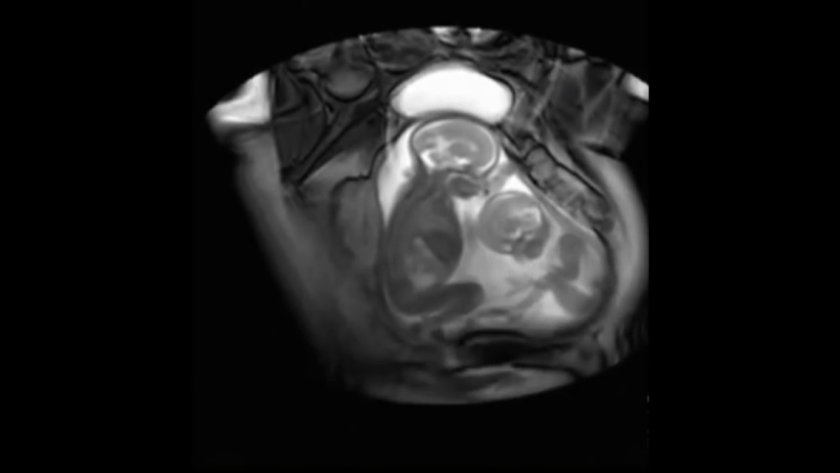

This incredible video shows two twin siblings appearing to be struggling to get comfortable inside the womb.

An MRI shows two babies as they are appearing to repeatedly fight and make up… Typical of siblings. Especially me and my sisters & brothers.

The bigger of the two appears to not only be getting more of the food, but more of the space.

It looks like these babies are already fighting, and making up, while in the uterus! It is amazing how much we can see in the womb today with modern technology. These images were taken from an MRI scan, or magnetic resonance imaging.

The details that can be seen are incredible, especially the way these two little people are moving around trying to get comfortable. It seems sibling rivalry has already begun in the womb, at one point one twin seems downright frustrated, and kicks repeatedly at the other baby. The way the baby on the left moves its head and jaw, (watch closely at 100) for a second, it very sweetly looks like it kisses the other baby on top of the head.

This scan was done as part of a medical study in London, and the pictures were taken while the researchers, and Dr. Marisa Taylor-Clarke, were studying a rare medical condition that affects twins.